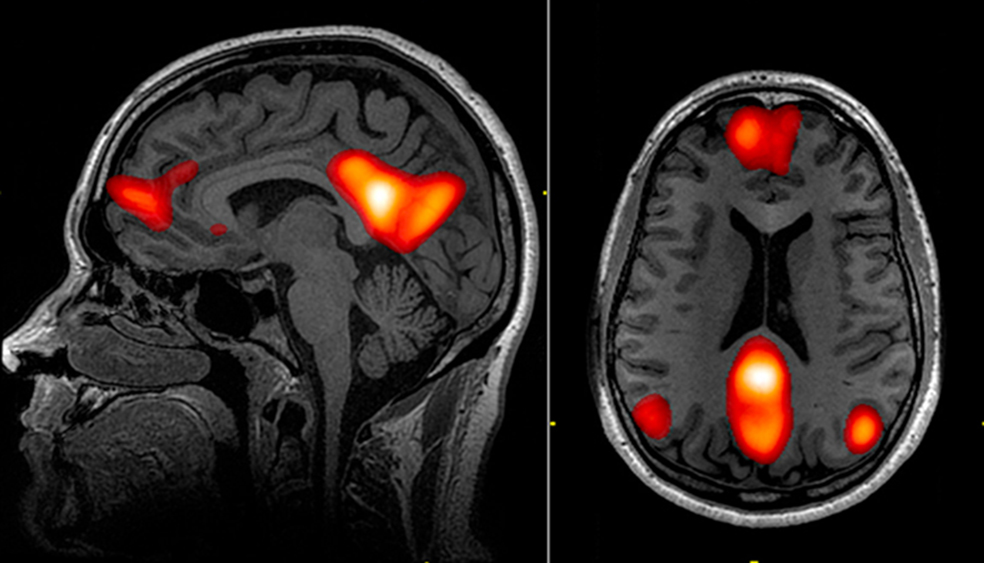

La responsable de este 'efecto ducha', en términos fisiológicos, es la red neuronal por defecto, una función de nuestro cerebro que se activa cuando entramos en modo 'desconexión'. Las resonancias magnéticas funcionales han permitido en los últimos años visualizar cómo la actividad de esta red se desarrolla en los lóbulos temporal, parietal y prefrontal. Cuando desconectamos o dejamos vagar nuestra mente, esa red se activa como una onda que fluctúa cada ciertos milisegundos. El cerebro relajado, por ponerlo en palabras sencillas, no se 'apaga' sino que se mueve en otra 'longitud de onda'.